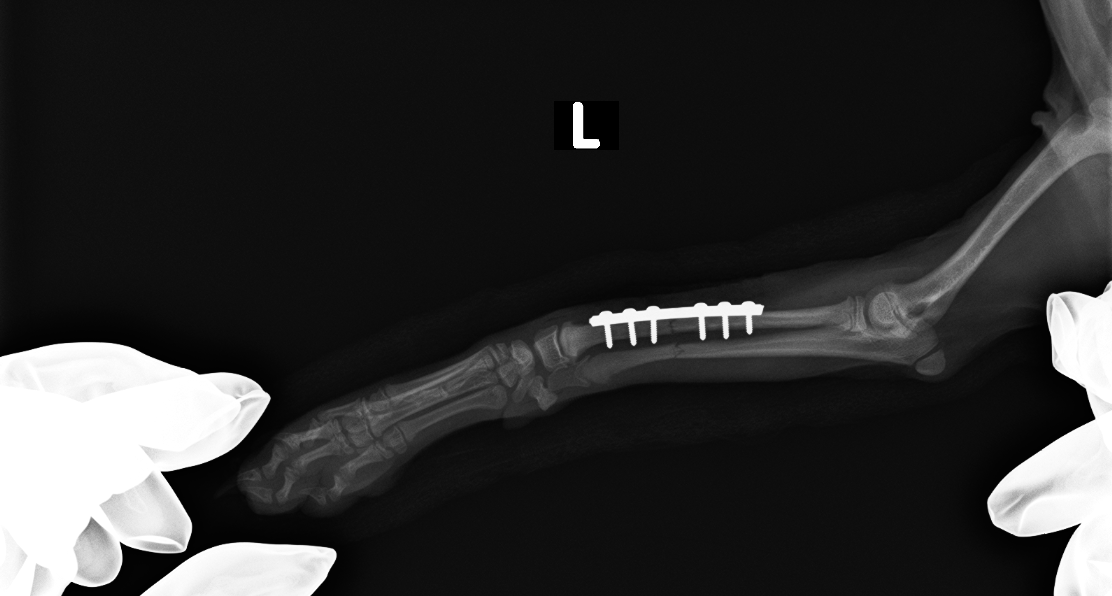

橈骨のプレート固定

after